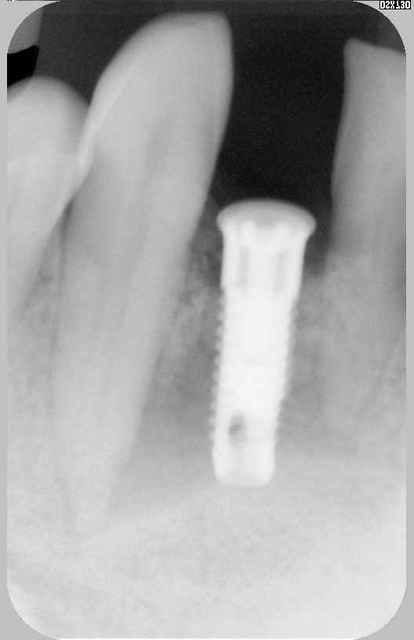

haaa bein voilà...fallait bien que çà arrive un jour...ptit cas tout chaud de cet aprèm...

faut dire que çà fait 2 ans que je ne l'ai pas vue...zéro pointé de maintenance...

hygiène bof...je l'avais pourtant prévenue!!!

l'implant en 22 va bien, l'image est bizarre du fait de son angulation...et s'il parait bien gros...c'est qu'il est bien gros (un 4.7/16!!!) car posé en EII et la racine de la 22 était énorme...

en 44/45 tout va bien, 34 lui aussi, 36 pas trop mal....mais 35!!!

bizarre quand même, j'ai sondé, pas de perte en lingual mais perte de 3mm en vestibulaire...

je l'ai mise sous AB, fait un bon nettoyage/aéropolissage, dit de bien reprendre l'hygiène, et rdv pour contrôle dans un mois...